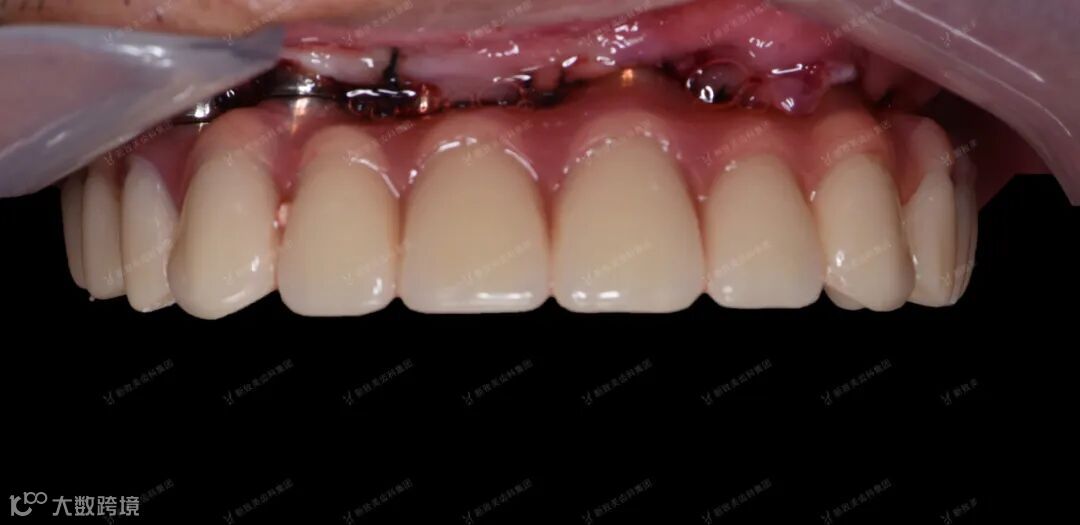

患者带牙后口内照